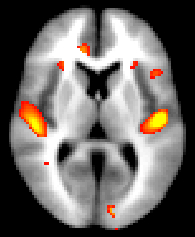

Obtaining and displaying your FSL-VBM results

We strongly recommend using randomise (permutation testing) for inference in VBM-style analysis and not Gaussian random field theory (GRF), as the approximations underlying the latter are not generally appropriate in such analyses.

Running randomise and displaying TFCE-based thresholding results

You can then view the (1-p) corrected p-value images in FSLView:

before displaying it with fsleyes overlaid on the template_GM or the MNI152 template for example: